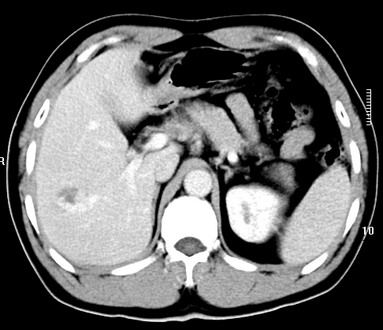

标题: CT19720:肝右叶血管瘤。肝左叶内侧段病灶考虑什么? [打印本页]

标题: CT19720:肝右叶血管瘤。肝左叶内侧段病灶考虑什么?

男,48岁,肝区不适月余,伴隐痛。

支持右叶血管瘤,左叶病灶考虑肝腺瘤。

1)不排除肝左叶肝癌。2)肝右叶血管瘤。

肝左叶炎性病变,肝癌待排。2)肝右叶血管瘤。

1.肝右叶血管瘤;2.肝左叶炎性假瘤?肝癌?建议穿刺活检.

右叶病灶典型,左叶病变慢性炎块

1、肝右叶血管瘤(典型)。

2、肝左叶病灶,强化不明显,疑炎性假瘤,建议结合临床并密切随访。

1、肝左叶炎性病变,肝癌待排。

2、肝右叶血管瘤。

肝左叶脓肿,肝癌待排。2)肝右叶血管瘤